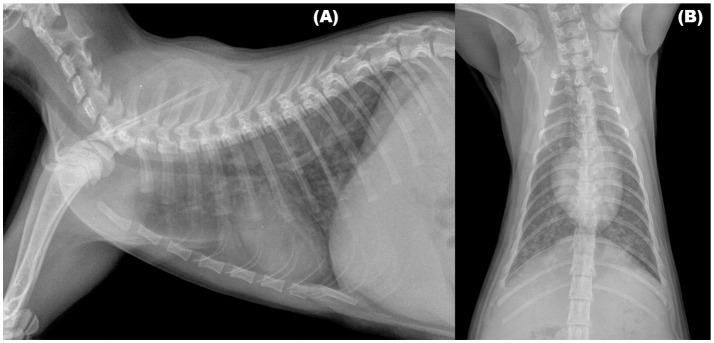

Parasitic bronchopneumonia plays an important role in feline respiratory medicine, thus it is receiving growing attention by researchers and practitioners. In recent years, , a lungworm usually infecting wild felids, has been recognized as an agent of the lower respiratory tract in domestic cats. In particular, as a likely consequence of a spill-over from wild reservoirs (e.g., the European wildcat), infection is increasingly reported in cats from Mediterranean and Balkan countries. This parasitic nematode has an indirect life cycle, and its biology overlaps that of the better known "cat lungworm" . In fact, cases of co-infections caused by both lungworms are not infrequent in domestic cats. Knowledge on clinical features of troglostrongylosis is still incomplete. Available data indicates that clinical signs and radiographic evidence are severe especially in kittens and young cats, are non-specific and often overlap with those of other feline respiratory diseases, such as feline bronchial disease/asthma, or infectious pneumonia. These characteristics make a definitive diagnosis of troglostrongylosis challenging, this disease requires a timely ancillary therapy and an appropriate anthelminthic treatment. As feline troglostrongylosis is an emerging parasitic disease of domestic cats, it should be included in differential diagnosis for lower respiratory tract disease in cats from regions where this parasite is present but also where it is unexpected. This article reviews current knowledge on the pathogenic role of in domestic cats and resulting respiratory illness, with a special focus on clinical aspects, diagnosis, and management of the disease.

寄生性支气管肺炎在猫科动物呼吸医学中起着重要作用,因此受到研究人员和从业者越来越多的关注。近年来,一种通常感染野生猫科动物的肺线虫已被确认为家猫下呼吸道的病原体。特别是,作为野生宿主(如欧洲野猫)溢出的可能后果,在地中海和巴尔干国家的猫中越来越多地报告了感染情况。这种寄生线虫具有间接的生命周期,其生物学特性与更为人所知的“猫肺线虫”重叠。事实上,两种肺线虫引起的合并感染在家猫中并不罕见。关于管圆线虫病临床特征的知识仍然不完整。现有数据表明,临床症状和影像学证据在小猫和幼猫中尤为严重,是非特异性的,并且常常与其他猫科动物呼吸道疾病(如猫支气管疾病/哮喘或传染性肺炎)的症状重叠。这些特征使得管圆线虫病的明确诊断具有挑战性,这种疾病需要及时的辅助治疗和适当的驱虫治疗。由于猫管圆线虫病是家猫中一种新出现的寄生虫病,在该寄生虫存在但也在意想不到的地区,它应被纳入猫下呼吸道疾病的鉴别诊断中。本文综述了目前关于 在家猫中的致病作用以及由此导致的呼吸道疾病的知识,特别关注该疾病的临床方面、诊断和管理。